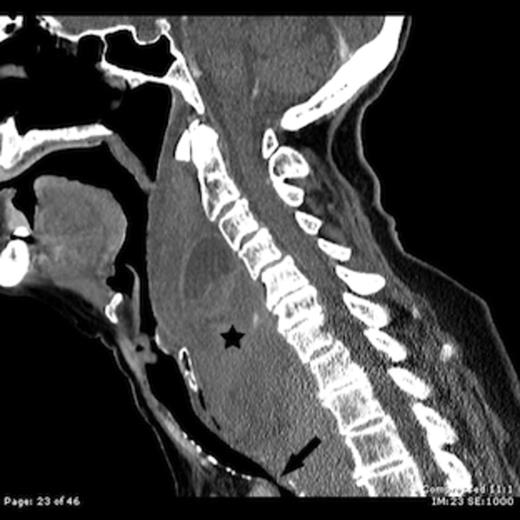

Computed tomography (CT) of the brain, neck and chest was performed. A massive retropharyngeal haematoma was observed extending between C2 and T4 vertebral body levels with displacement and compression of the trachea (Figure 1,2). There was no evidence of carotid, vertebral or internal jugular vein injury and no cervical fracture.

Contrast enhanced sagittal CT image shows a large retropharyngeal haematoma (star) extending from the C2 vertebral level to below the level of the sternal notch with tracheal compression (arrow)